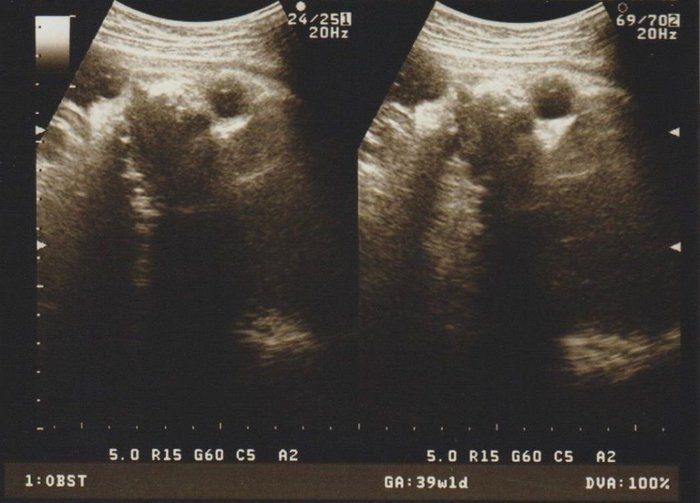

クリコさんの妊娠39週目のエコー写真

母や義母から「まだ生まれないの?」という電話と、たまたま出産予定日が日曜日で、夫、実父、義父も仕事が休み。その日に産まなきゃという義務感が生まれてきました。前日に自宅近くの坂道を上り下り、たっぷり散歩し、スクワットをした結果、無事、予定日当日に出産できました。